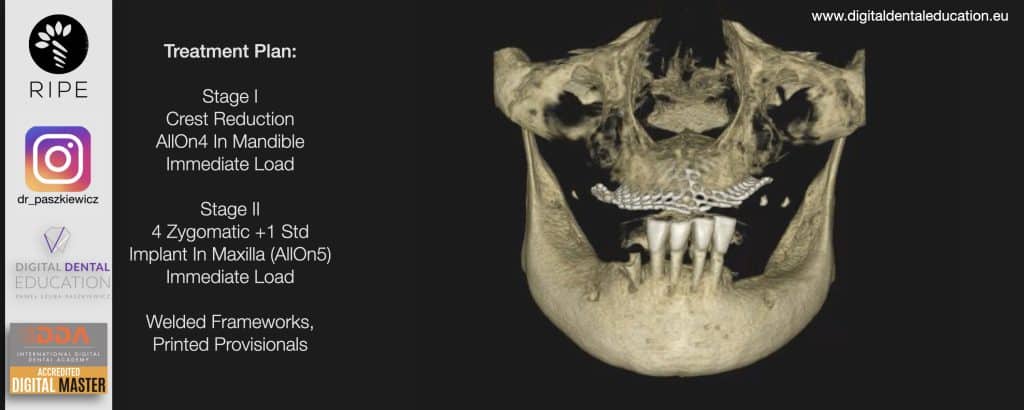

He has invented an AllonX non-impression protocol leading to final restorations post immediate implant full-arch loading, incorporated with desktop scanner (MEDIT) and ModJaw capturing of natural patient’s functional and mastication movements.